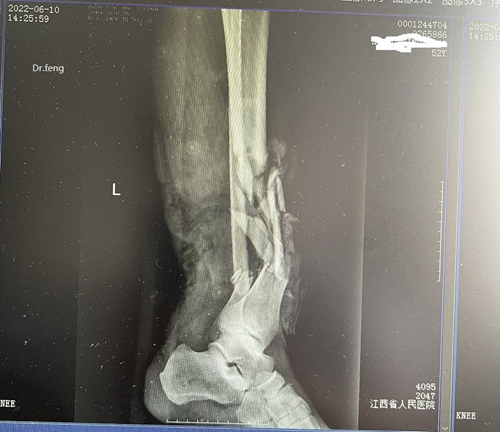

2022年6月10日,黄先生(化名)在工作时左下肢被三吨多重电线杆砸伤,造成下肢骨头碎裂、血管断裂、肌肉糜烂,皮肤完全撕脱,情况十分危急。工友立刻护送他到当地医院救治,接诊医生在查看病人后,认为损伤严重,需要转到上级医院治疗。经推荐黄先生转诊到江西省人民医院(南昌医学院第一附属医院)骨科一区冯子明主任医师医疗团队。

患者伤处影像